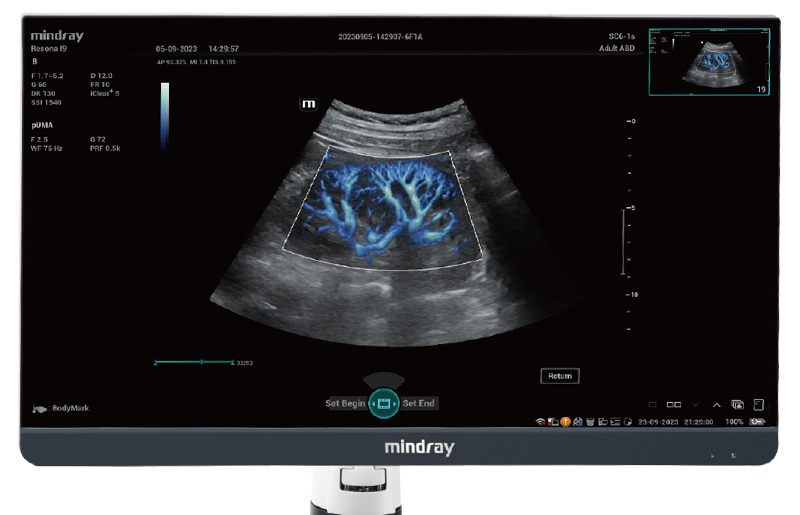

Für die Ultraschalltechnologie stellt die ZST+-Plattform einen bedeutenden Fortschritt dar, da sie statt der herkömmlichen Strahlformung die Kanaldatenverarbeitung verwendet. Diese bahnbrechende Innovation löst übliche Zielkonflikte zwischen räumlicher Auflösung, zeitlicher Auflösung und Homogenität des Gewebes auf, woraus sich eine beispiellose Bildqualität ergibt, die den Weg frei macht für unendlich viele Bildgebungslösungen.

Das Resona I9 weist umfassende klinische Lösungen für spezielle Anwendungen auf. Auf der Grundlage gründlicher Analysen verschiedener klinischer Szenarien liefert es Innovationen, die den Benutzenden herausragende Klarheit, außergewöhnliche Intelligenz und eine erhöhte Diagnosesicherheit bieten.